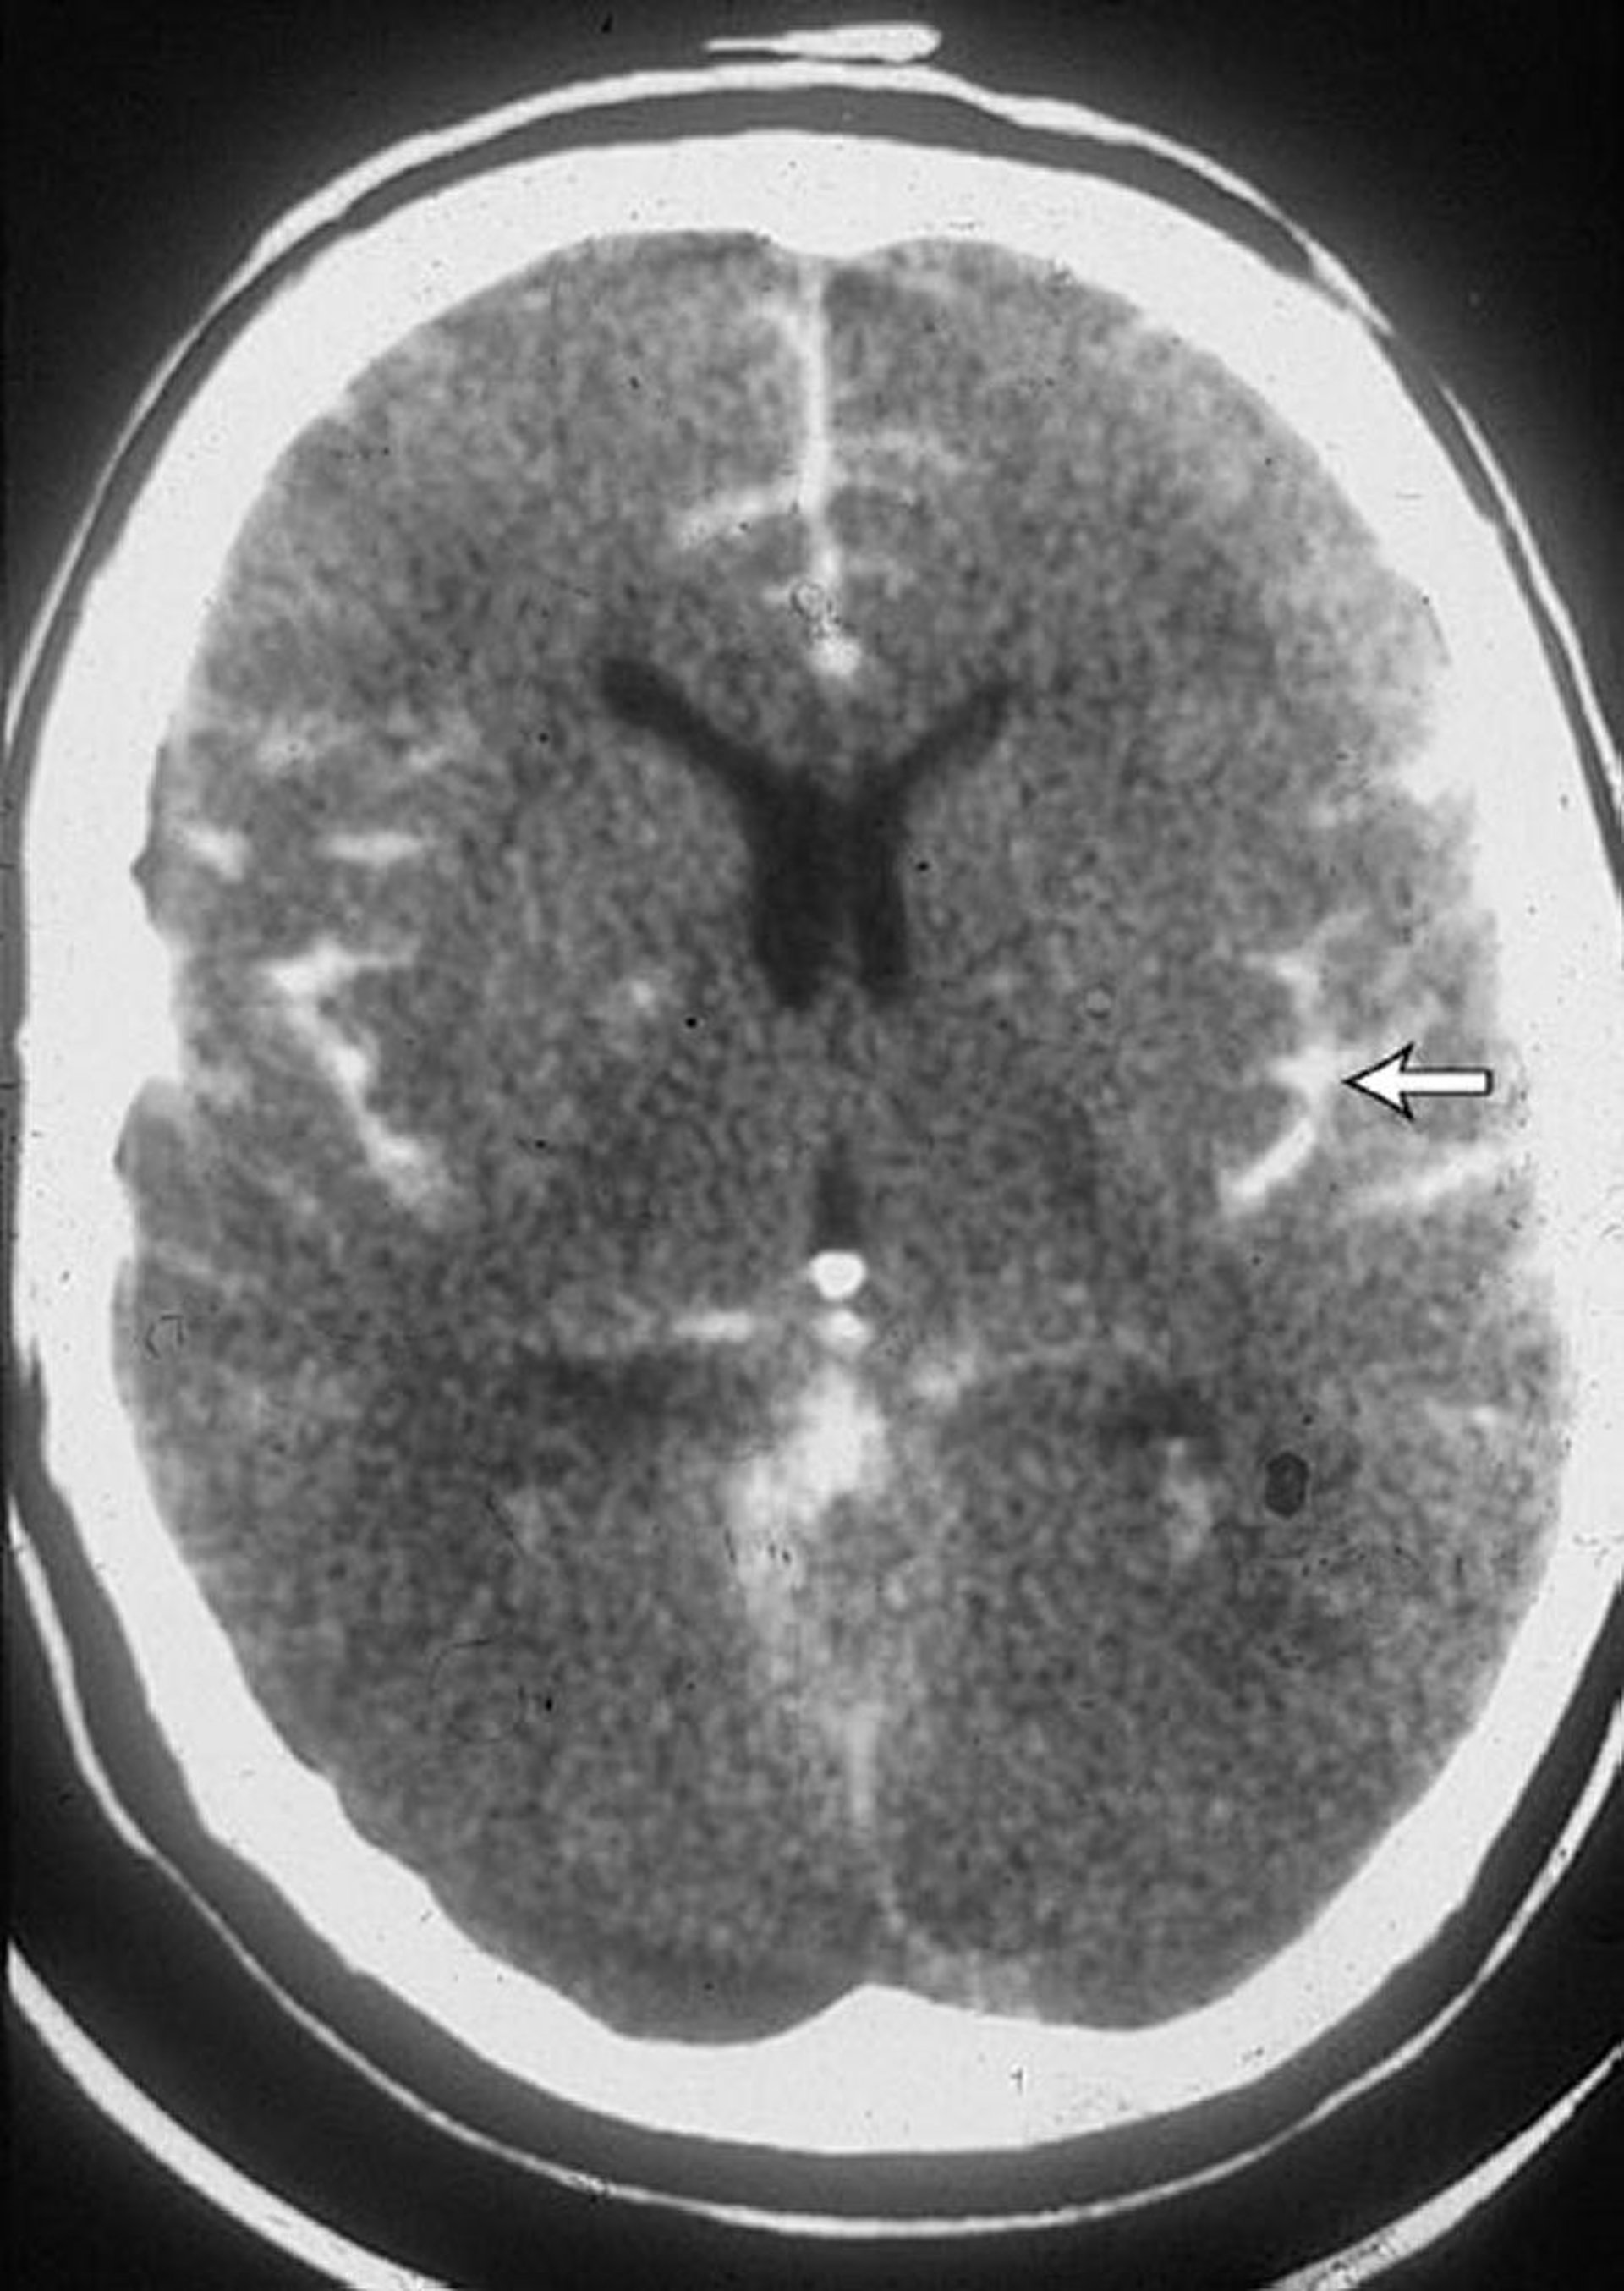

Emorragia subaracnoidea

Questa scansione TC in un paziente con un'emorragia subaracnoidea mostra sangue nei solchi (freccia). Del sangue è spesso visibile anche nei ventricoli.

By permission of the publisher. From Lenaerts M, Couch J. In Atlas of Clinical Neurology. Edited by RN Rosenberg. Philadelphia, Current Medicine, 2002.